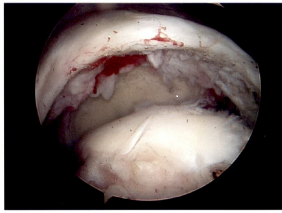

There are a number of different procedures based on the pathology. Generally, with partial thickness tears that have not responded to non-operative treatment the choice is arthroscopic surgery with debridement (shaving of the frayed tissue) of the rotator cuff often combined with removing bone spurs on the underside of the acromium. If there is significant arthritis in the ac joint that is symptomatic, a short section of the end of the clavicle may be removed at the same time. When a patient has a full thickness tear, the options are arthroscopic or mini-open rotator cuff repair. There is still debate about which procedure is more effective. In general, the quality of the open repair when tunnels are made in the bone (interosseous tunnels) has been felt to be stronger earlier in the healing process. Arthroscopic repair is dependent on inserting anchors in the bone to which sutures are attached. New arthroscopic devices and suture anchors, combined with a double row of anchors technique, have improved the quality of the repair. The only time an open repair is indicated is when bone tunnels are planned but if one is going to use anchors with an open incision, there is more trauma to the tissues than arthroscopic repair and overwhelmingly shoulder surgeons would not employ that technique. Post-operative sling immobilization and physical therapy rehabilitation is an integral part of the recovery to allow the tendon to heal to the bone. In the long run the repairs seem to have equivalent results with success of repair and range of motion. The advantage of the arthroscopic repair is the use of smaller incisions, decreased invasiveness (no muscles split) and the presumed decreased stiffness in the early postoperative phase. It is however important to note that some of rotator cuff repairs have some retearing of the tendon within one year of surgery, most without any symptoms because only a small portion of the repair retears. There is no correlation between the integrity of the repair and the resolution of patient symptoms. There are some rotator cuff tendons that cannot be repaired because the muscles have atrophied too much or the tendons have retracted or fibrosed and cannot physically be repaired. There is also the chronic situation where the lack of rotator cuff function has led to a severe type of arthritis called rotator cuff arthropathy which is amenable to a specific type of shoulder joint replacement.